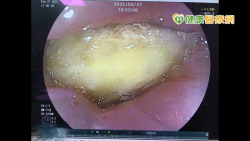

挺台灣鳳梨 男整塊卡食道 醫師緊急內視鏡夾出

洪弘昌院長表示發生食物噎到之意外時,應停止進食,實施哈姆立克急救法,並安排就醫由專業醫師協助。 中國近日宣布禁止台灣鳳梨銷往中國之事,許多民眾紛紛力挺台灣鳳梨,南投縣的鳳梨擁有濃郁香氣,酸酸甜甜,品質一級棒。一名年約47歲李先生也想以行動來支持,週末時與朋友騎單車至南投受命宮附近短暫休憩時,購買鳳梨並當場享用,當下覺得胸前有東西堵住感,吞不下去,喝水也...... [閱讀更多]